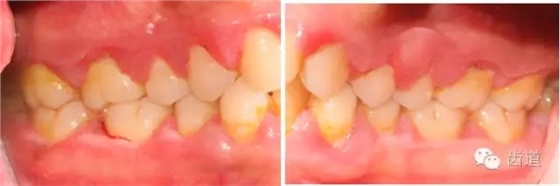

1、口腔衛(wèi)生狀況及局部刺激物(牙菌斑、牙石,不良修復(fù)體)

牙石及不良修復(fù)體

2、牙齦

(顏色、形狀、質(zhì)地、退縮、BOP、PD、附著齦)